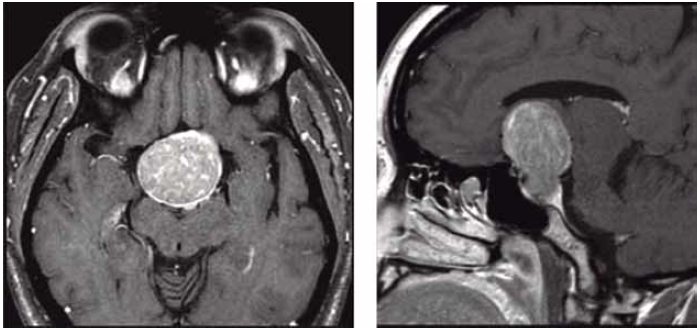

Mulher de 35 anos apresenta quadro de cefaleia e embaçamento visual. A ressonância magnética realizada é mostrada a seguir.

(Arquivo pessoal; imagem usada com autorização)

Qual o achado que, mais provavelmente, deve ser encontrado no exame físico?